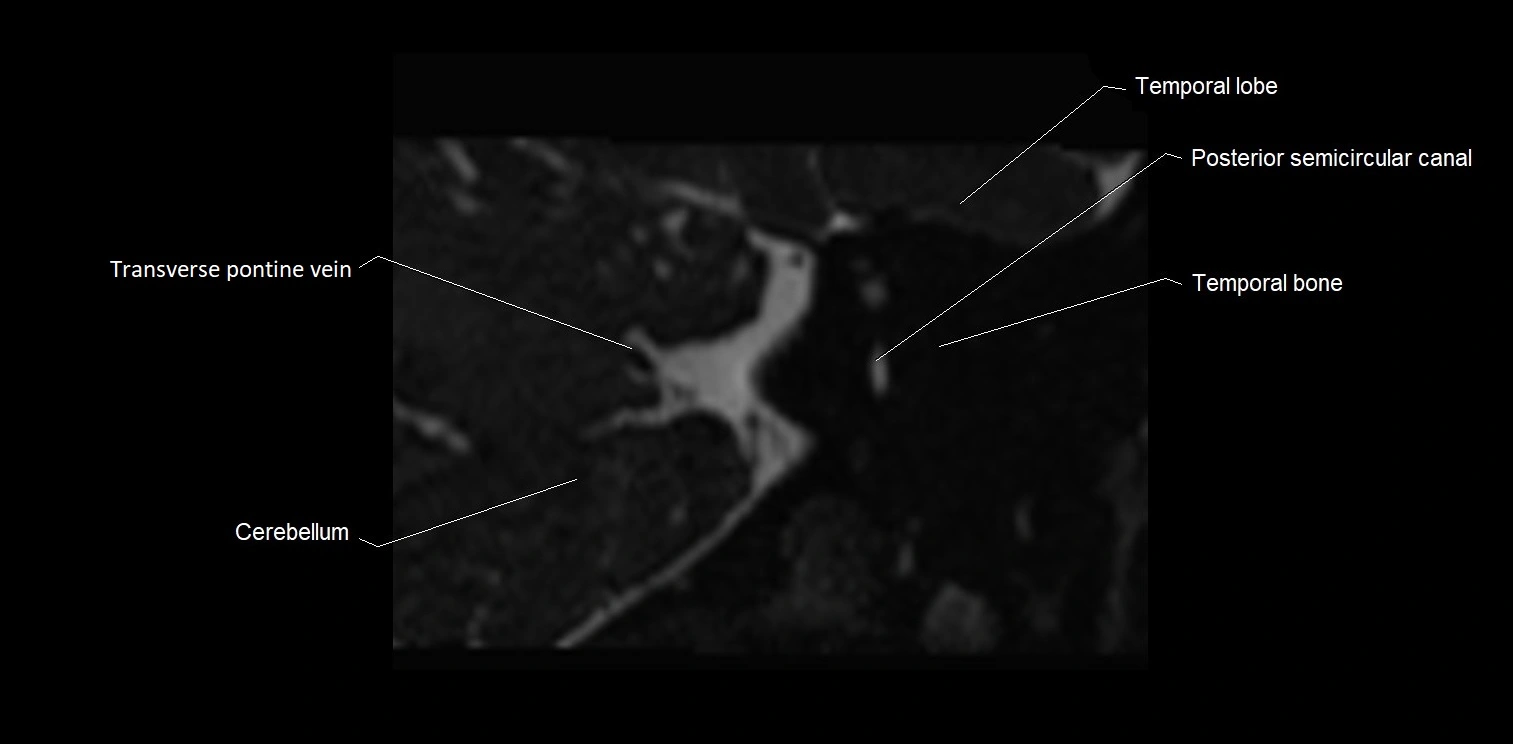

image